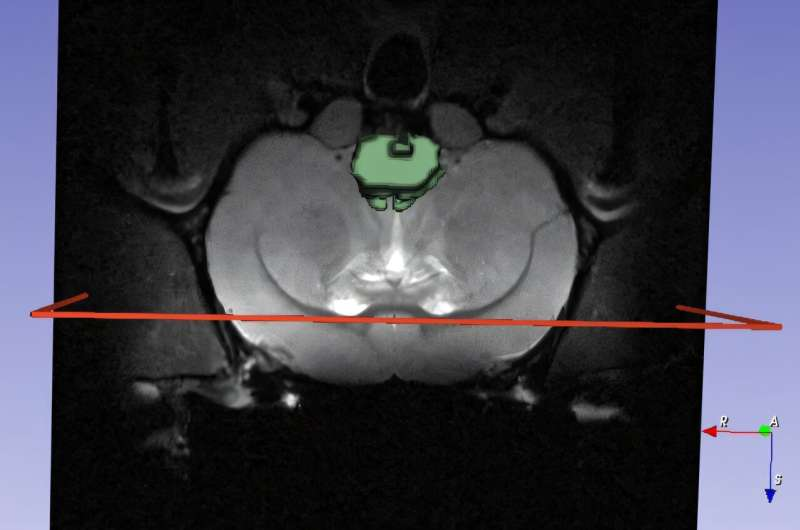

Credit: OpenNeuro

This is where molecular imaging—including MRI (Magnetic Resonance Imaging) and PET (Positron Emission Tomography)—comes in. These techniques let scientists track nanomedicines in real time, visualize their distribution, and observe their biological impact.